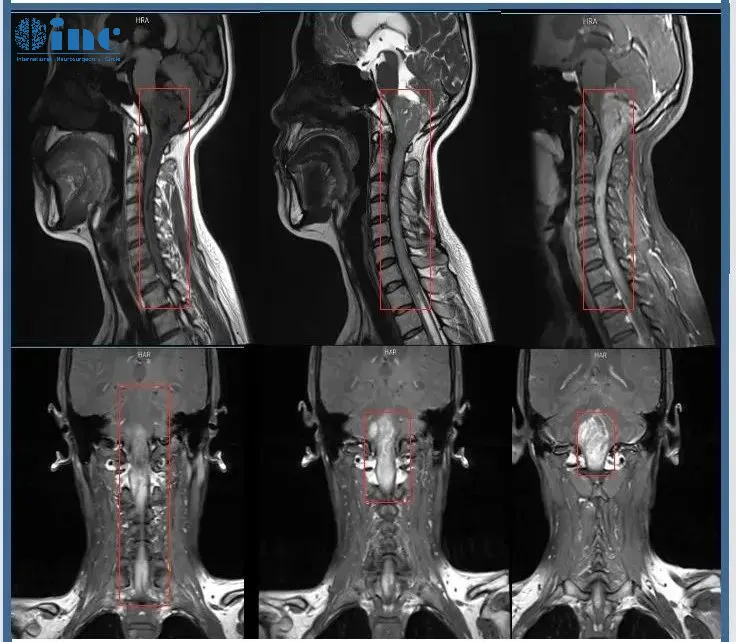

术前MR

看着影像片子上这条长度可怕的肿瘤,同为医务工作者的郑女士非常清楚手术的风险,脑干是生命中枢,脊髓是连接大脑与周围神经系统的主要通路,其中一处长肿瘤,不管肿瘤带来的威胁还是手术的风险,都是难以想象的,何况自己的这条病变范围累及15cm的大肿瘤。能安全手术的主刀医生也非常少,在查阅了许多专业的医学资料后,郑女士将目光锁定在国际脑干手术专家——INC德国巴特朗菲教授身上。看着年幼的孩子,和身边为自己担忧的爱人,郑女士决定寻求他的示范手术……

“影像资料显示非常广泛的髓内肿瘤,起源于脑干下部,受累延髓和颅颈交界区-且向下方延伸到整个颈部脊髓以及一直到第一胸椎水平。我以前成功地做过类似巨大肿瘤患者的手术,但是我必须说明,这种巨大肿瘤的切除术非常费力和耗时,就像两台独立的手术,因为不仅是肿瘤的切除需要时间,而且还要行广泛的椎板成形术(从颈1到胸1水平)以及枕下开颅术。病人应该在肿瘤比现在小的时候更早接受手术。手术是可行的,也是必要的。”